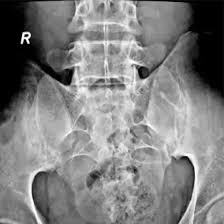

An x-ray of the SI Joint AP and Oblique is a diagnostic imaging procedure used to evaluate the sacroiliac (SI) joints, which connect the pelvis to the lower spine. The X-ray offers two key perspectives:

The AP (Anteroposterior) View provides a straight front-to-back view of both SI joints. The oblique view enables a more thorough analysis of anomalies.

The test can help clinicians diagnose SI joint misalignment, arthritis, fractures, and inflammatory disorders.Why is it Done?

An X-ray Both SI Joint AP & Oblique Scan combines front (AP) and angled (oblique) views of the sacroiliac joints to give a more complete picture of the joint space, alignment, and surrounding bone structures. It’s used to diagnose inflammation, arthritis, or structural abnormalities causing lower back or pelvic pain.

An X-ray Both SI Joint AP & Oblique can detect sacroiliitis, joint misalignment, arthritis, fractures, and degenerative changes in the sacroiliac joints. It provides a detailed view to diagnose chronic lower back or pelvic pain accurately.